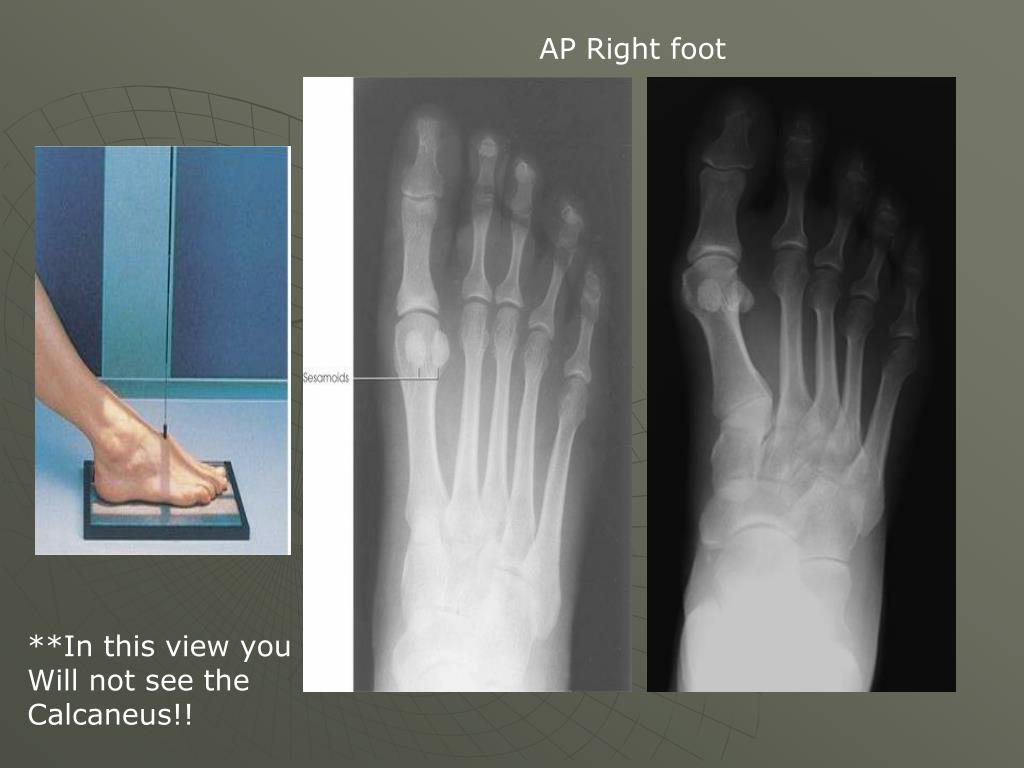

18. AP Right foot **In this view you Will not see the Calcaneus!!

19. Structures shown: • Dorsoplanter (AP) projection of the tarsals anterior to the talus, the metatarsals,and the phalanges • You will not see the whole calcaneus on this view. Why? • Some people angle 10 degrees toward the heel on this view ***You want all of the phalanges, metatarsals and tarsals distal to the talus on your image

20. Check film for: • Motion • Rotation: there will be overlap of second- fifth metatarsal bases • Open joint space between medial and intermediate cuneiform • No overlap of toes • Density- are the toes burned out